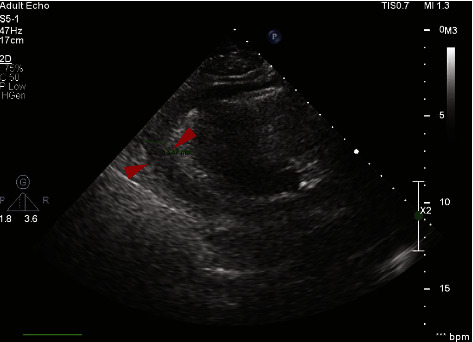

Introduction: The introduction of Bruton's tyrosine kinase (BTK) inhibitors significantly improved the management of chronic lymphocytic leukemia (CLL). However, BTK carry the risk of cardiotoxicity, which is not only limited to atrial fibrillation. Case Reports. We report three cases of patients on BTK inhibitors who developed acute pericarditis and cardiac tamponade. We report the first patient who developed this complication on treatment with zanubrutinib. This patient's treatment was changed to zanubrutinib due to atrial fibrillation. Shortly after cardioversion, he developed cardiac tamponade and shock. He underwent pericardiocentesis, received treatment for acute pericarditis with steroids and colchicine, and made a full recovery. We also report two further cases, both involving patients treated with ibrutinib. These patients also developed acute pericarditis and cardiac tamponade and required pericardiocentesis. All three patients discontinued BTK therapy following the events.

Conclusions: These three cases highlight the rare but potentially life-threatening risk of cardiac tamponade which can occur even with newer generations of BTK inhibitors. Haemato-oncologists should remain vigilant in patients who report dyspnea or who show sinus tachycardia on routine electrocardiography. Even in the absence of classical clinical signs of tamponade, patients require urgent evaluation with echocardiography and potentially emergency pericardiocentesis.